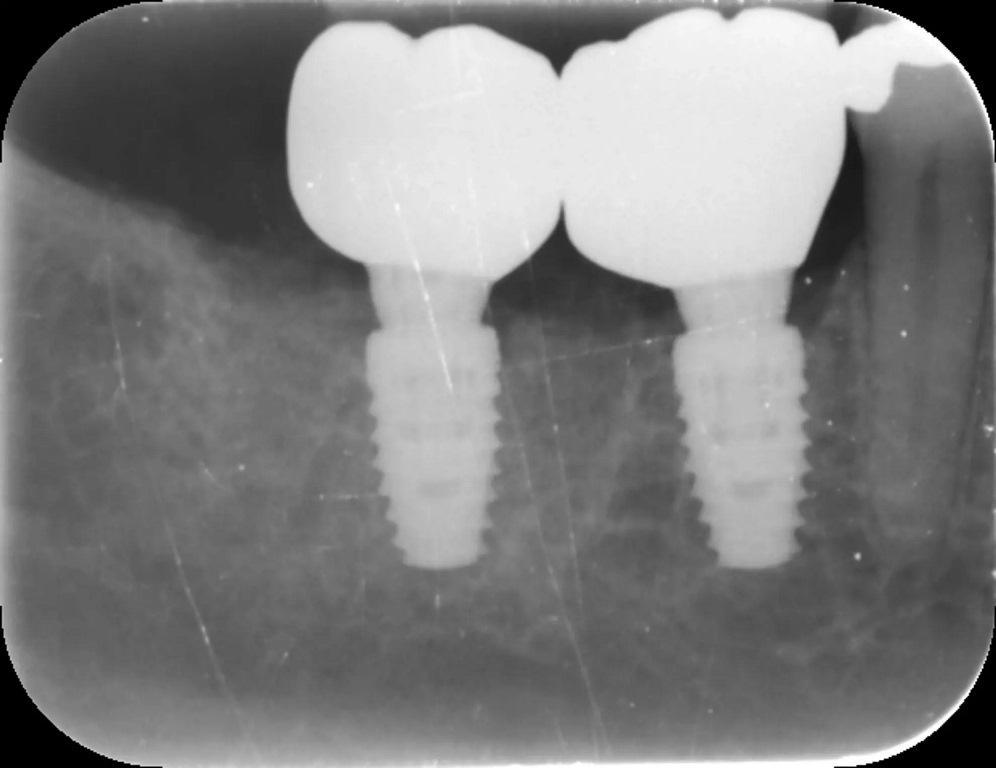

Прошло три месяца после заживления. Для определения положения имплантата и профиля мягких тканей использовался интраоральный сканер Medit i700, он обеспечивает оптимальное планирование протезирования и точную реставрацию (фото 12). Коронки-имплантаты были изготовлены с использованием специально отфрезерованных титановых абатментов с циркониевой коронкой. Любой диоксид циркония, контактировавший с тканью, был отполирован, а не покрыт глазурью, чтобы обеспечить оптимальное здоровье мягких тканей.

Фото 12: Послеоперационная рентгенограмма.

Немедленная имплантация CONELOG PROGRESSIVE-LINE в обе лунки коренных зубов прошла гладко, обеспечив превосходную первичную стабильность. Твердые и мягкие ткани были в хорошем состоянии и были достигнуты превосходная толщина мягких тканей и устойчивая полоса ороговевшей ткани (фото 13–16). Такой подход не только сохранил существующие кости и мягкие ткани, но и заложил прочную основу для будущего протезирования. Этот случай подчеркивает важность выбора метода, имплантата и трансплантационного материала для оптимизации долгосрочных результатов в имплантологической стоматологии.

Использование аллотрансплантата для костной трансплантации MinerOss Putty сыграло решающую роль в поддержании объема кости и целостности мягких тканей, что в дальнейшем способствовало долгосрочному успеху имплантатов. Этот аллотрансплантат обычно выбирается в таких случаях. Его исключительные эксплуатационные свойства облегчают установку. Кроме того, благодаря 10%-ному составу коллагена, он обеспечивает превосходную интеграцию, снижая риск миграции частиц или плохого сцепления при размещении, что наблюдается при использовании других трансплантационных материалов.